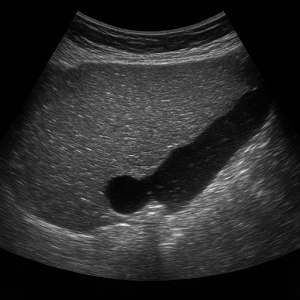

신장은 결석, 수신증(소변이 막혀 고여서 생긴 변화), 낭종, 종양 등의 상태를 초음파로 볼 수 있어요. 부신은 위치가 작고 깊지만, 우연종 같은 병변이 의심될 때 관찰할 수 있답니다.

신장 결석, 신부전, 낭종

- 신장 결석

콩팥에 생긴 작은 돌들은 초음파에서 반짝이며 그림자를 동반해 쉽게 보일 수 있어요. - 신부전 (수신증 등)

소변이 막혀서 신장이 붓는 상태를 ‘수신증’이라고 하는데요, 초음파로 신장의 부종이나 이상을 확인할 수 있어요. - 신장 낭종이나 종양

주머니처럼 생긴 낭종이나 덩어리가 있으면 초음파로 확인 가능해요.

소변에 피가 섞여 나오면 신장이나 요로에 문제가 있을 수 있어요. 혈뇨의 원인이 될 수 있는 신장 결석, 낭종, 종양, 수신증(소변이 막혀 신장이 부어오르는 상태) 등을 복부초음파로 확인할 수 있어요.